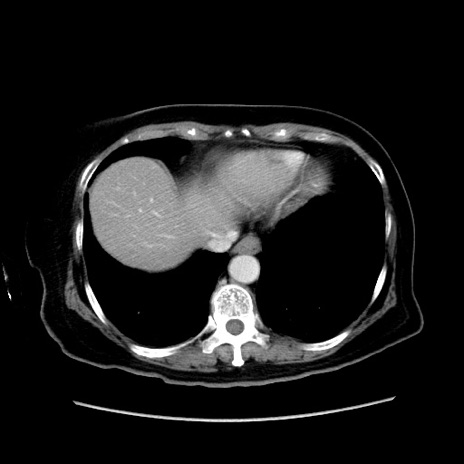

冠状断像

【症例】80歳代女性

【主訴】下腹部痛

【現病歴】約8時間前より下腹部痛の出現あり、救急外来受診。

【既往歴】両側付属器切除

【身体所見】意識清明、下腹部正中に手術痕あり、その部位に一致して圧痛と反跳痛あり。腸蠕動音は亢進。

【データ】WBC 9300、CRP 0.15